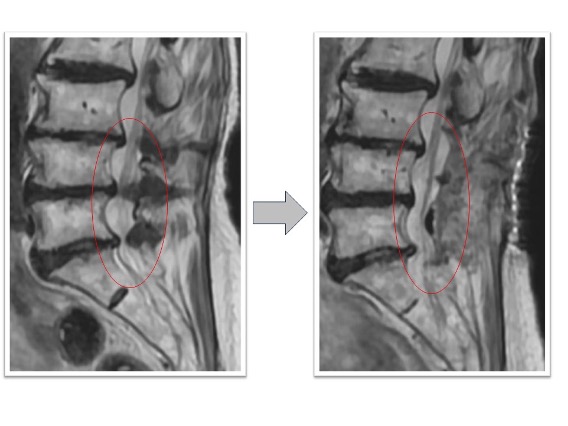

頚椎椎弓形成術実例(*患者様の許可を得て掲載しています)

頚椎症性脊髄症

上肢の運動障害、歩行障害の患者様に対して頚椎椎弓形成術を実施。術後MRI画像で頚髄の圧迫が解除され頚髄前後にスペースが生まれています(図赤丸)。また、CT画像では術前後の比較で脊柱管の前後幅が約1.5倍以上に拡大していることが確認できます(図青矢印)。術後は歩行安定し、上肢運動も改善しています。